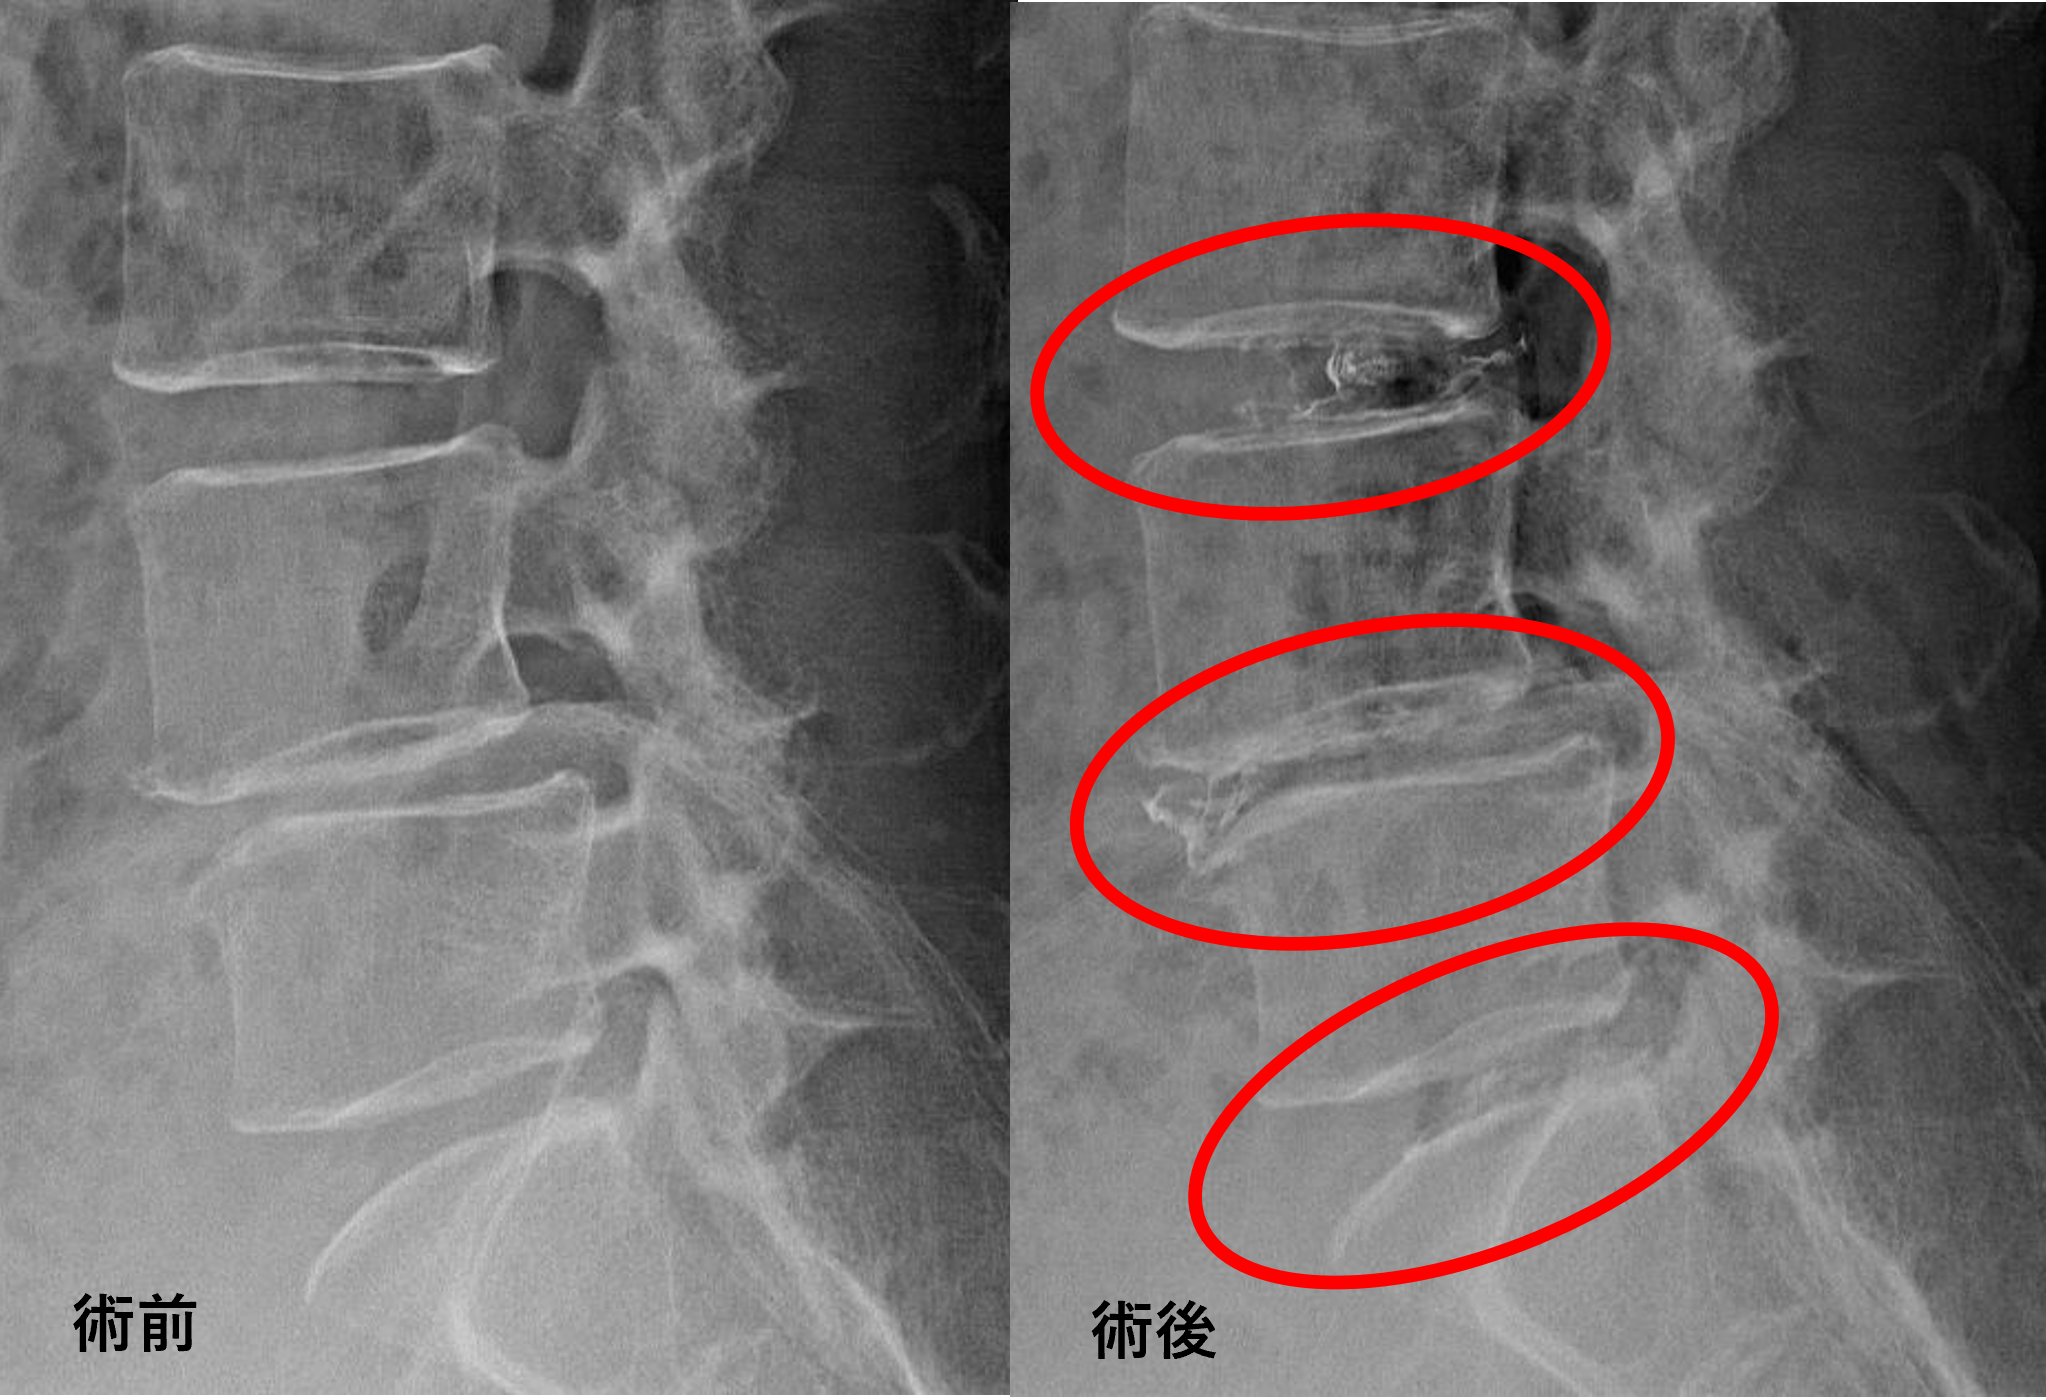

患者様と相談の元、L3/4、4/5、5/sにセルゲル法を施行

治療は35分程度で終了

回復室で休憩後、歩いて帰院されました。